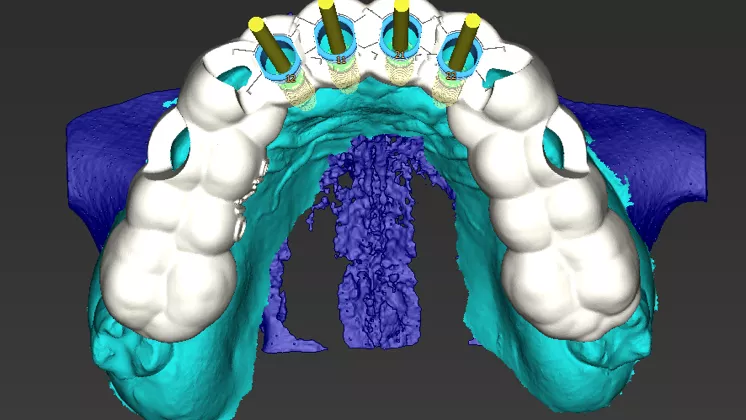

07 - Anterior rehabilitation using Narrow GM implants through guided and digital workflow

Dr. Geninho Thomé